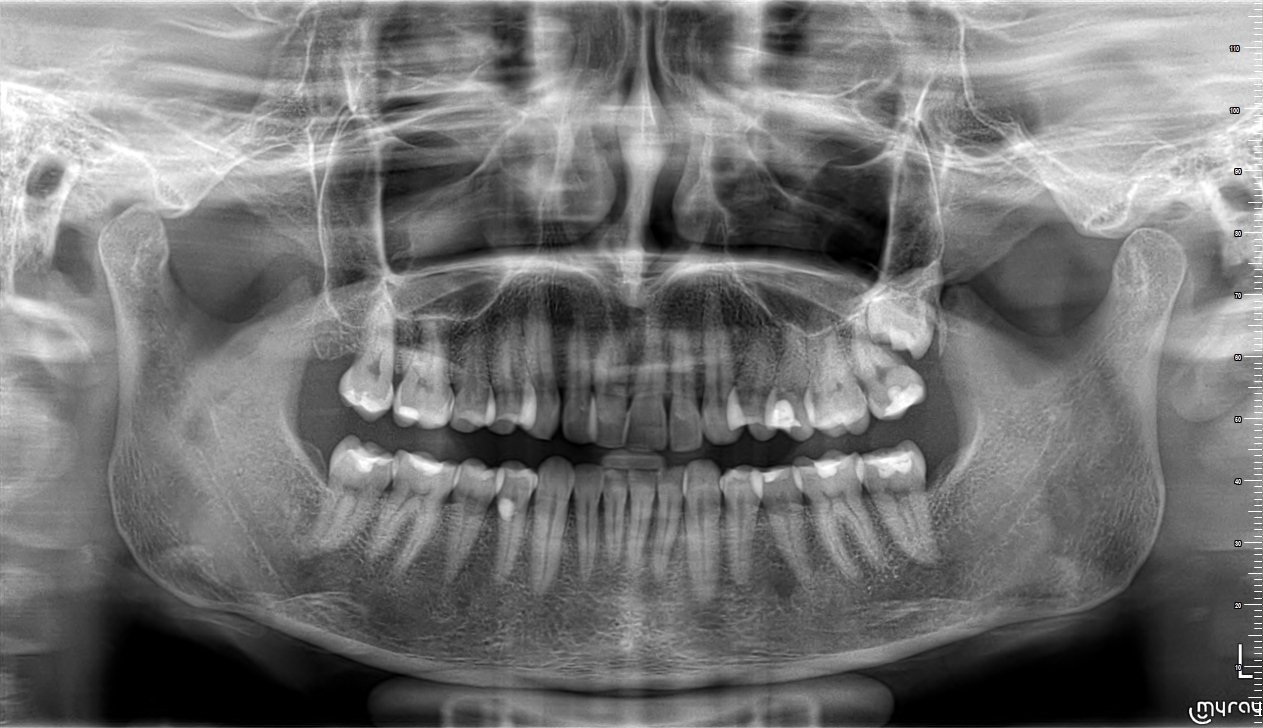

Здравейте, случайно при снимка по друг повод ми откриха ретиниран мъдрец. До този момент не съм имала оплаквания и не съм знаела за неговото съществуване. Може ли да ми кажете дали се налага да го извадя и евентуално крие ли рискове в бъдеще. Прилагам рентгенова снимка. Благодаря предварително.

По тези снимки не е възможно да се прецени в каква посока е мъдреца. Може да е пред или зад съседни зъб. Най-добре се вижда на СВСТ (3д рентген). Ако не ви създава проблеми и ако не притиска седмицата - по-добре не го пипайте.